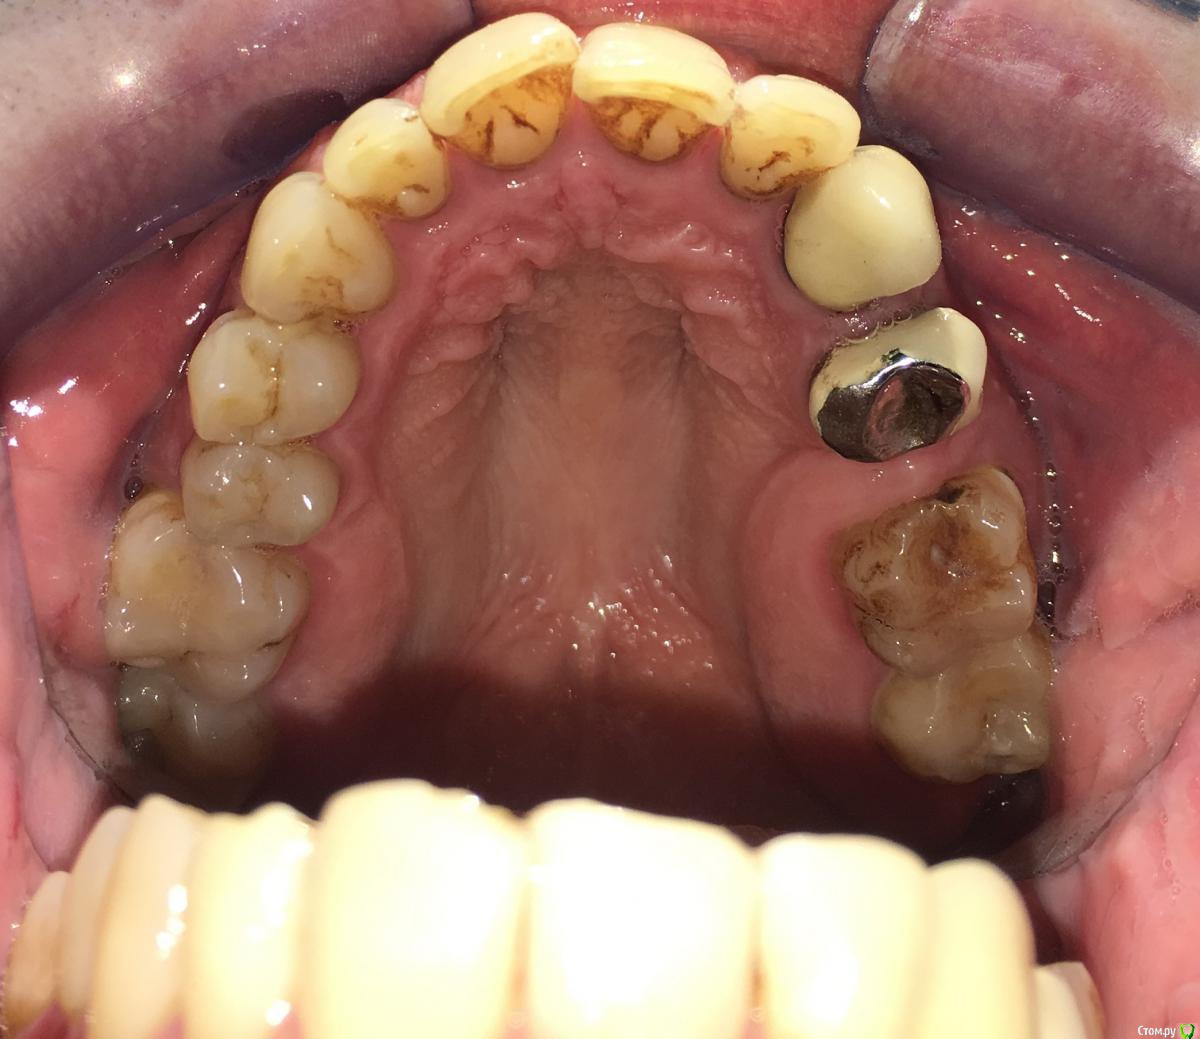

Nitrino1 Опубликовано 20 января, 2018 Поделиться Опубликовано 20 января, 2018 Коллеги помогите поставить правильный диагноз и составить план лечения, чтоб продолжительно держалосьОбъективно на всех зубах камни над и поддесневые. В 47ом зубе 3-я степень подвижность.Почистил все камни и налеты, назначил полоскание, пасту Парадонтах, удалил 47ой зуб.Сделал панорамку (до удаления) и фотки тоже до удаления.Должен составить план лечения... Ссылка на комментарий

red_butler Опубликовано 21 января, 2018 Поделиться Опубликовано 21 января, 2018 Хронический генерализованный пародонтит тяжелой степени, в ремиссии (по МКБ-10 Хронический генерализованный пародонтит, код К0531) Ссылка на комментарий

Nitrino1 Опубликовано 21 января, 2018 Автор Поделиться Опубликовано 21 января, 2018 Хронический генерализованный пародонтит тяжелой степени, в ремиссии (по МКБ-10 Хронический генерализованный пародонтит, код К0531)какой план лечения вы бы порекомендовали? интересует момент с нижними резцами, их шинировать или же удалить? на верхних 6ках тоже ситуация не очень. Вообще какую тактику выбрали бы?И еще просьба, посоветуйте что можно почитать современное на тему парадонтитов и парадонтозов, то что у меня есть это старое уже Ссылка на комментарий

almaz7888 Опубликовано 3 февраля, 2018 Поделиться Опубликовано 3 февраля, 2018 Шинирование нижних резцов в связке с соседними зубами после предварительно го депульпирования зубов. В последующем лоскутная операция. Избирательное пришлифовывание. 1 3 Ссылка на комментарий

molchanoff Опубликовано 4 февраля, 2018 Поделиться Опубликовано 4 февраля, 2018 Удалить подвижное. Кюретаж того что останется. Два съемника и убедившись в стабилизации процесса имплантация. Ссылка на комментарий

almaz7888 Опубликовано 4 февраля, 2018 Поделиться Опубликовано 4 февраля, 2018 Удалить подвижное. Кюретаж того что останется. Два съемника и убедившись в стабилизации процесса имплантация.Вряд ли съемник поспособствует стабилизации процесса. Будет атрофия в области удаленного зуба плюс расшатаются опорные зубы, за счетгоризонтального направления сил. Если уж удалять и протезировать, то делать бюгельный протез с шинирующими элементами. 1 Ссылка на комментарий

chervoncevdaniil Опубликовано 5 февраля, 2018 Поделиться Опубликовано 5 февраля, 2018 (изменено) Удалить подвижное+гигена/кюретаж+остальные коронки+кламмерный бюгель.Сейчас вам могут написать про тотальную имплантацию с объемные костными пластиками и т.д,вы конечно это все внимательно прочитайте,пациенту обязательно предложите и посчитайте приблизительную стоимость,огласите сроки и если вдруг окажется(ну мало ли ),что к такому протезированию он не готов,обсудите вариант с бюгелем,пусть даже как временный,чтобы он собирал деньги на имплантацию в перспективе(но по опыту этот вариант окажется и постоянным) Изменено 5 февраля, 2018 пользователем chervoncevdaniil 1 Ссылка на комментарий

Nitrino1 Опубликовано 13 февраля, 2018 Автор Поделиться Опубликовано 13 февраля, 2018 Удалить подвижное+гигена/кюретаж+остальные коронки+кламмерный бюгель.Сейчас вам могут написать про тотальную имплантацию с объемные костными пластиками и т.д,вы конечно это все внимательно прочитайте,пациенту обязательно предложите и посчитайте приблизительную стоимость,огласите сроки и если вдруг окажется(ну мало ли ),что к такому протезированию он не готов,обсудите вариант с бюгелем,пусть даже как временный,чтобы он собирал деньги на имплантацию в перспективе(но по опыту этот вариант окажется и постоянным)Пока что шинировал фронтальные подвижные зубы с помощью ретейнера. Пока наблюдаю и переделываю коронки) тотальную имплантацию не предлагаю)) Ссылка на комментарий